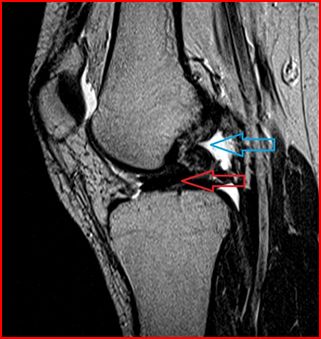

Lateral Stabilizing Structures Of The Knee: Functional ...

Knee, anatomy, 452.121411, 452.92 • Knee, injuries, 452.485 • Knee, ligaments, menisci, and cartilage, 452.485, 452.92 conjoined tendon which extends from the fabella (open arrow) to the styloid process of the fibula (not shown). Solid arrow = fibular attachment of the biceps ... Read More